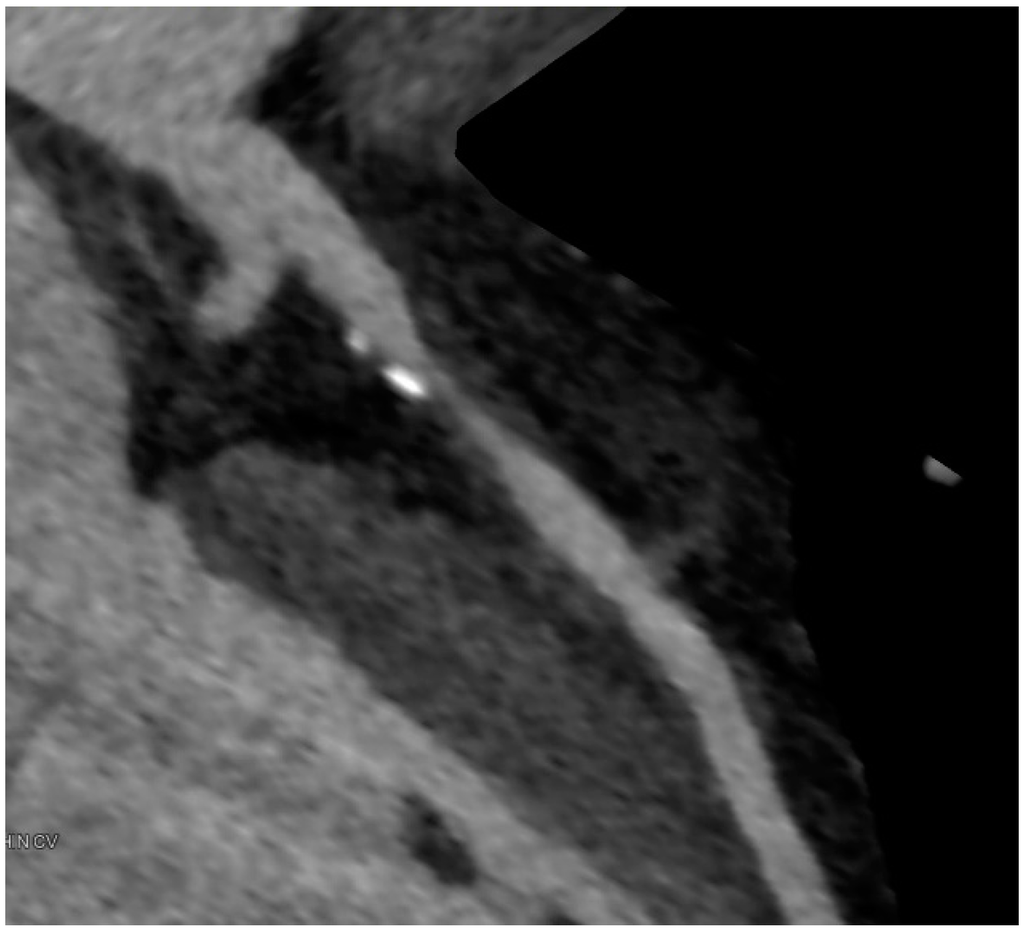

7. Qualitative Plaque Characterization

8. Hemodynamic Relevance of Angiographic Stenoses